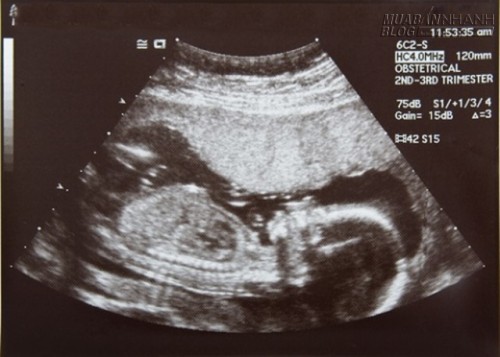

Lịch siêu âm thai định kỳ mẹ bầu cần nhớ

Tuy nhiên, nếu khám đầu đủ thì phải là 7 lần đối với một thai kỳ bình thường. Dưới đây là lịch khám thai định kỳ các mẹ bầu cần phải biết.![]()

Bước sang tuần 21 – 22, dù sản phụ vẫn cảm nhận được sự lớn lên từng ngày của thai nhi nhưng vẫn cần được thăm khám và siêu âm hình thể của thai nhi nhằm phát hiện những dấu hiệu bất thường (nếu có). Thời điểm này, bà mẹ có thể được siêu âm 3D hay 4D để phát hiện những bất thường về hình thể thai nhi3 tháng giữa là thời điểm lý tưởng để thực hiện các phẫu thuật, thủ thuật sản phụ khoa thích hợp mà không ảnh hưởng đến sự phát triển của thai nhi hoặc không làm cho sanh non như khâu vòng cổ tử cung ở những bà mẹ bị hở eo tử cung, phẫu thuật bóc hoặc cắt khối u buồng trứng ở những bà mẹ có khối u buồng trứng.

Ở tuần 31 đến 32, sản phụ vẫn tiến hành khám, theo dõi và làm siêu âm lần cuối cùng. Cũng trong lần khám này, người mẹ sẽ được tiêm mũi uốn ván lần 2.3 tháng cuối là lúc các bà mẹ sắp sanh mà các tai biến sản khoa thường xảy ra khi sinh, trong chuyển dạ. Do đó, khám thai vào thời điểm này là để chẩn đoán ngôi thai, sự tương xứng giữa cân nặng thai nhi và khung chậu người mẹ… từ đó có thể tiên lượng được cuộc sanh sắp tới dễ hay khó, có nguy cơ gì? Ngoài ra những thai kỳ nguy cơ cao đã có thể phát hiện được và từ đó cho nhập viện sớm trước ngày dự sanh.